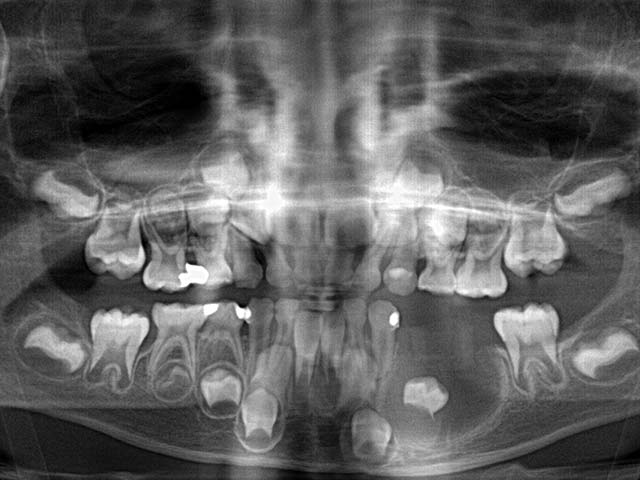

除此之外,兒童拍攝全口X光片還早期發現一些罕見疾病或先天缺牙如下:

2.左下及正中門牙先天缺牙

3.右下先天缺牙第二大臼齒